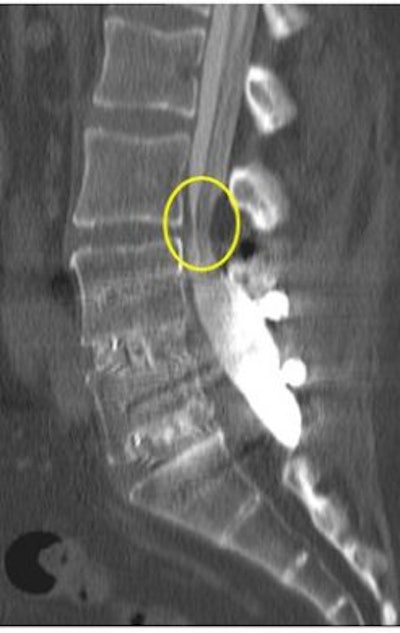

| Increased conspicuity of L4-L5 disk bulge and 2.0 mm increase in stenosis at the L4-L5 level with axial loading. |

A survey of patients from a private practice setting who underwent axial-loaded imaging demonstrated an increase in the conspicuity of focal disk bulging and herniation, as well as an increase an anterolisthesis or retrolisthesis ("Axial loaded magnetic resonance imaging of the lumbar spine in a chiropractic patient population," Proceedings of the 2006 Conference on Chiropractic Research, Chicago).

Dr. Akio Hiwatashi's group found that axial loading during MR imaging of the lumbar spine can influence treatment decisions for symptomatic spinal stenosis from conservative management to decompressive surgery based on the findings obtained from axial-loaded MR images (American Journal of Neuroradiology, February 2004, Vol. 25:2, pp. 170-174).